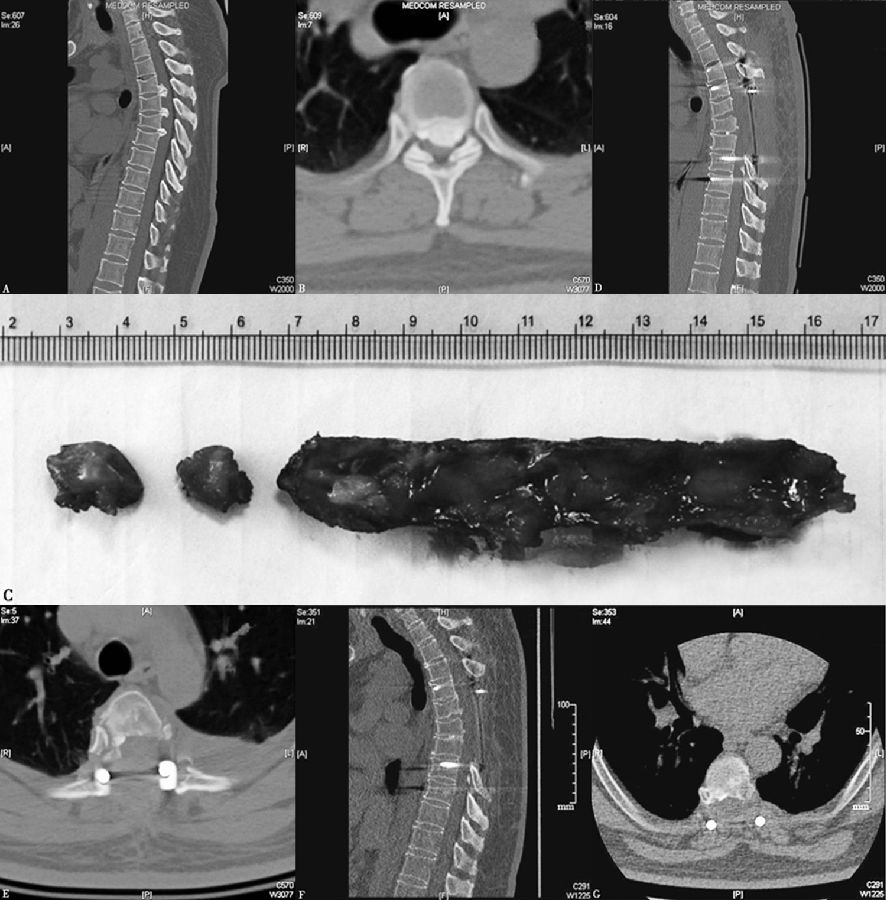

图2 后纵韧带骨化环脊髓减压

A、B、C:切除棘突及后方椎板;

B、D、E、F:切除侧方肋横关节及椎体后方骨质,达到充分减压的目的

图3 环脊髓减压病例:48岁男性患者后纵韧带骨化症(T4/5,T5/6,T6/7),行环脊髓减压

A、B:术前CT;C:术中切除骨化韧带及椎板;D、E:术后CT;F、G:术后3.5年随访复查CT